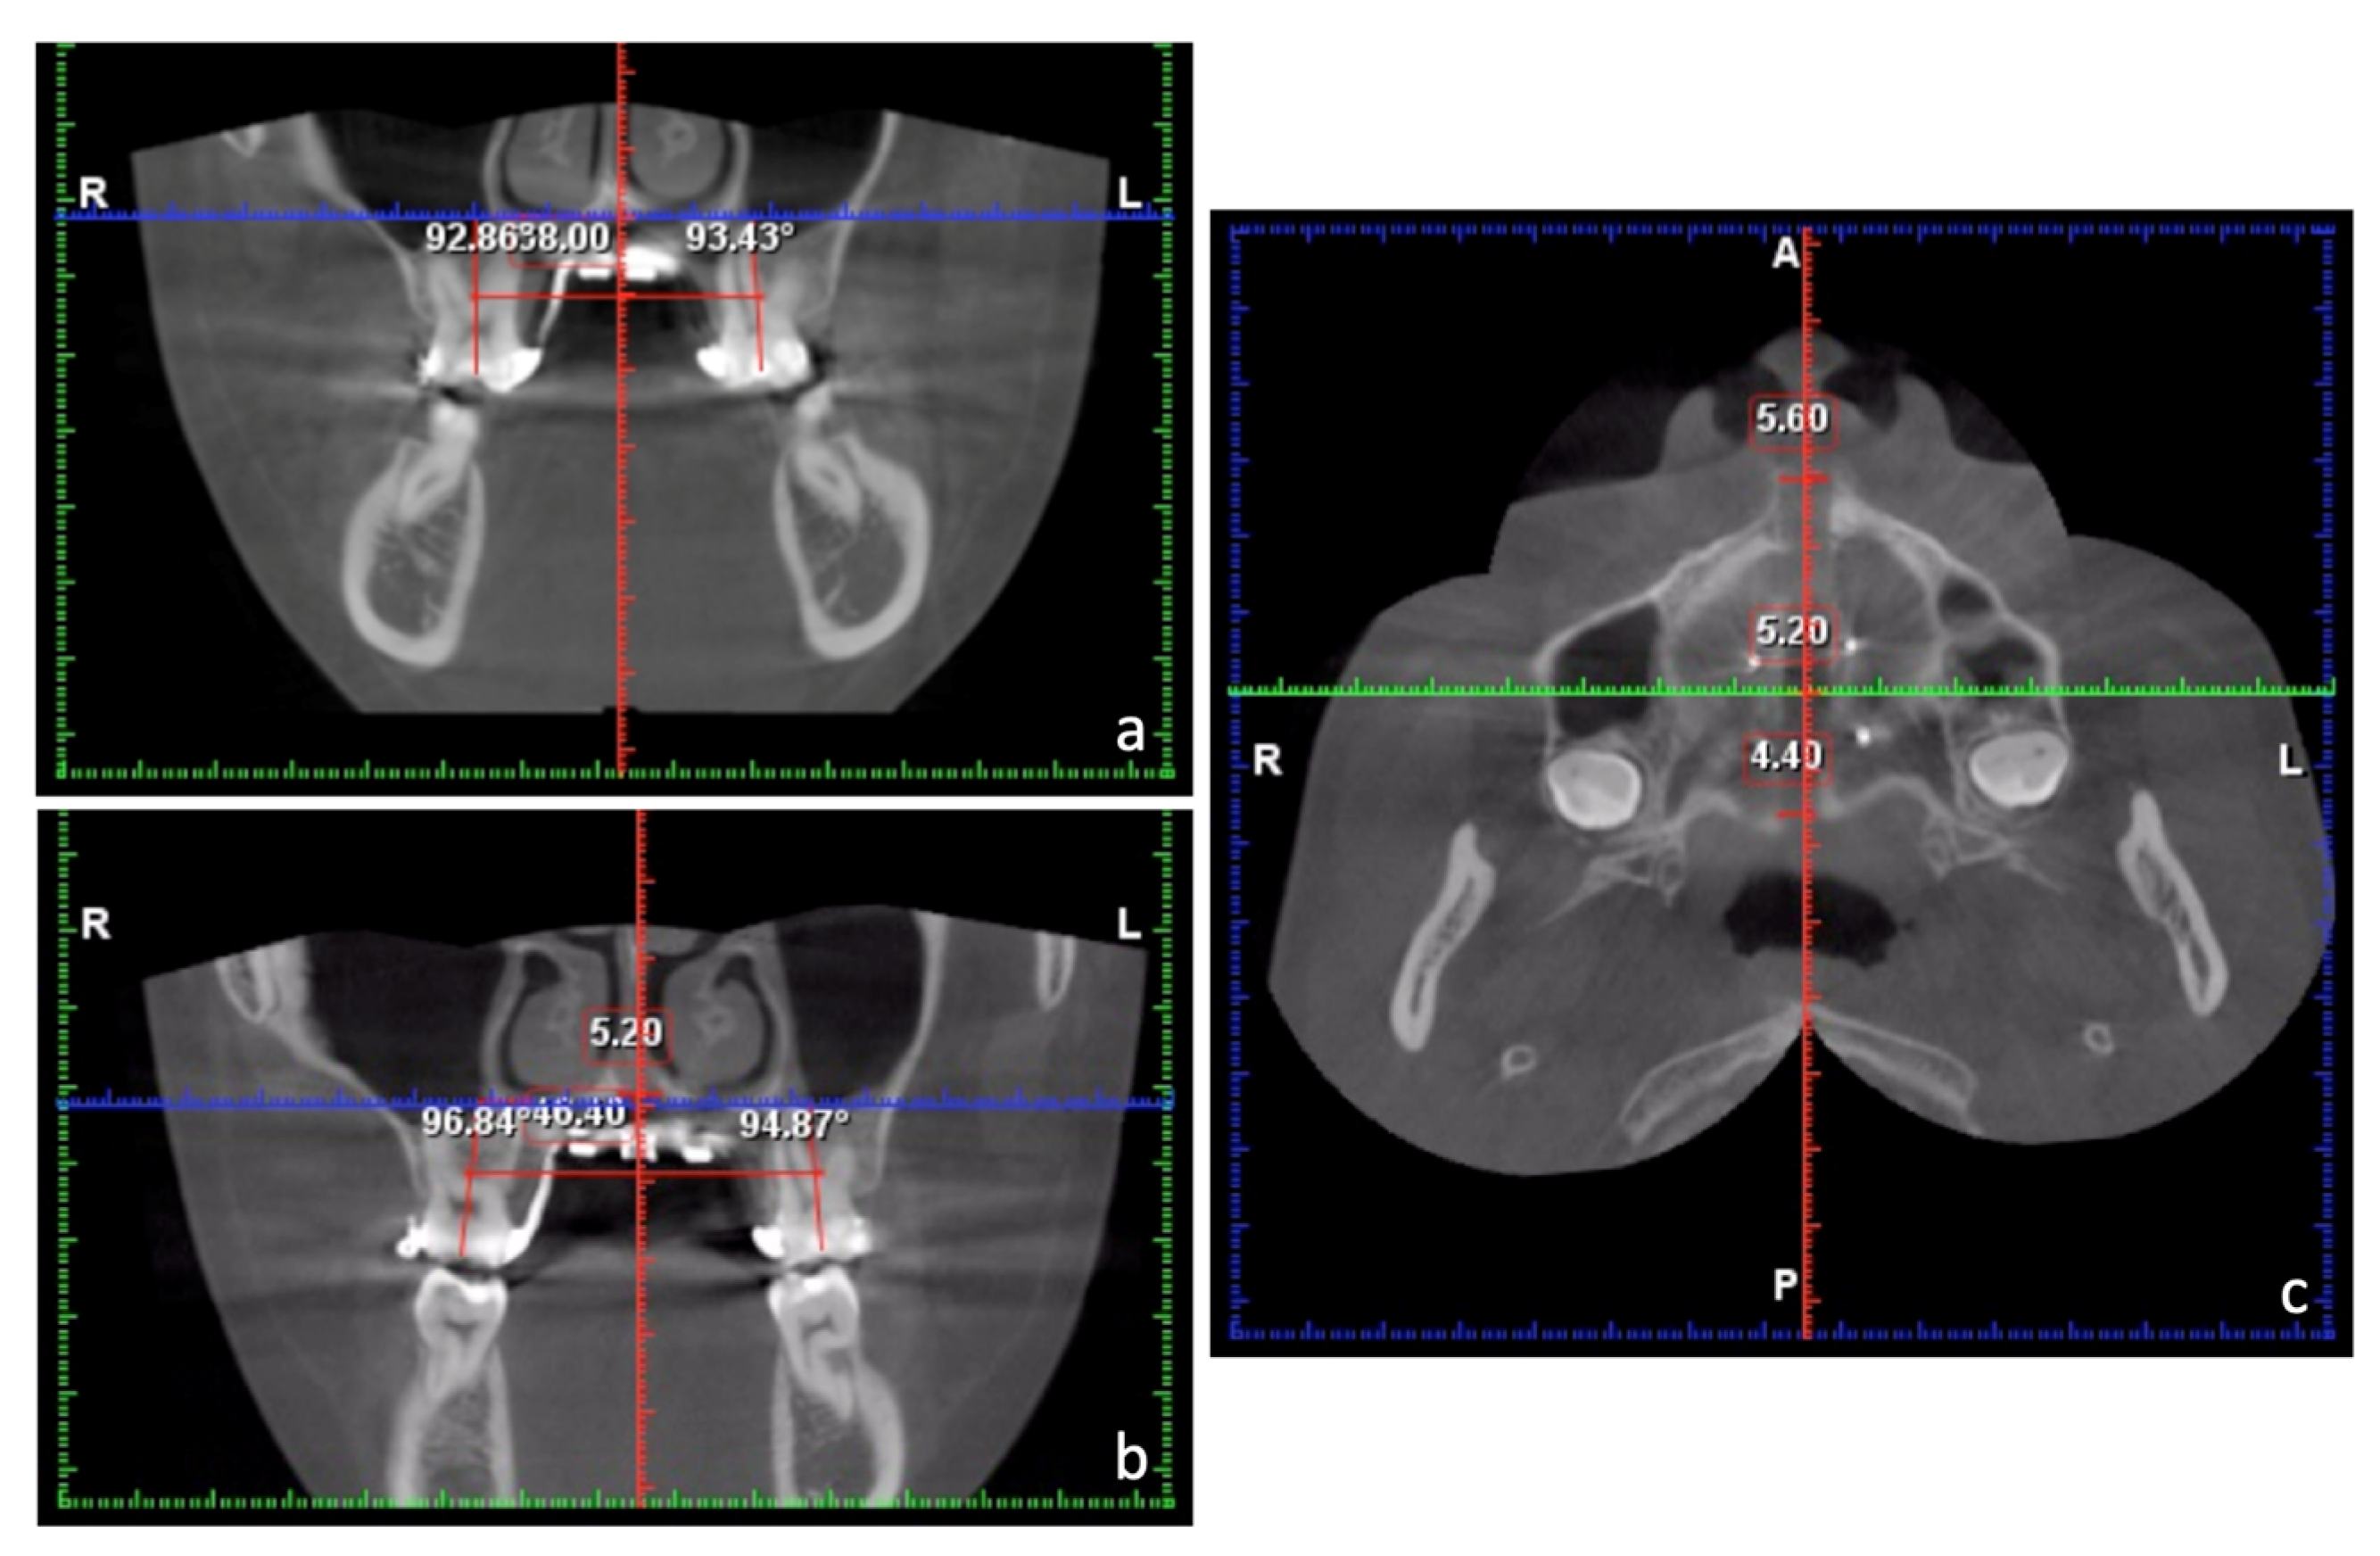

2. Case Report

2.1. Diagnosis and Aetiology

| JR-JL | 82.2 mm |

|---|---|

| AG-GA | 117.7 mm |

| Maxillomandibular transverse discrepancy | 35.5 mm |

| Expected transverse difference (14 y/o) | 18 mm |

| Maxillomandibular transverse differential index | 17.5 mm |